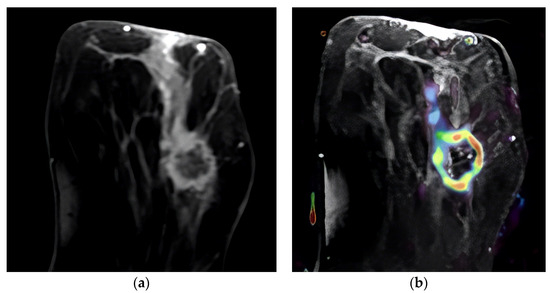

Figure 2.

T2-weighted MRI image that shows the tumor’s location in the axial slice (a). Perfusion mapping (red shows elevated perfusion) and progressive contrast change show washout in the tumor’s periphery (b).